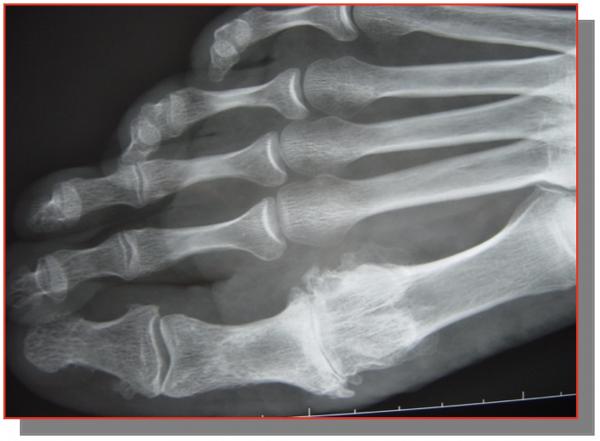

HALLUX VALGUS

Il s’agit d’une déformation qui crée une saillie osseuse sur la partie médiale de l’hallux, à l’origine de phénomènes douloureux et d’une gêne au chaussage. Il s’agit de la déformation la plus fréquente de l’hallux. Elle touche préférentiellement les femmes, parfois dès le plus jeune âge. On ne connaît pas réellement les causes de cette déformation mais l’origine congénitale semble la plus vraisemblable

DIAGNOSTIC :

Saillie douloureuse de la face interne de l’articulation métatarso-phalangienne déformation, bursite, douleur

Radiographie des pieds face et profil en charge +++ avant consultation d’un spécialiste,

Étude de l’architecture global du pied, de l’état articulaire à la recherche d’une arthrose, fracture de contrainte, et mesure des angles.